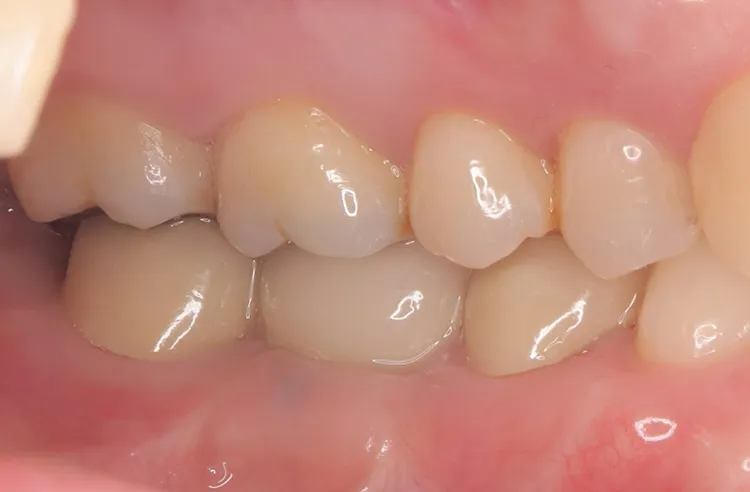

症例2/

臼歯1本

- 治療期間

- 3ヶ月

- 費用

- 51万円(税込)

治療前

治療後

レントゲン画像

治療内容

第一大臼歯1歯欠損をインプラントで回復したケースです。第一大臼歯は永久歯の中で一番最初に生える歯ですが、一番早く傷んでしまう歯でもあります。噛む力の60%を負担し噛み合わせの安定に大きく影響しますので、この歯が欠損すると噛み合わせに悪い影響を与えてしまいます。インプラントで治すことにより噛み合わせが安定するだけでなく、ブリッジのように隣在歯を削らないので天然歯の寿命を延ばすメリットもあります。